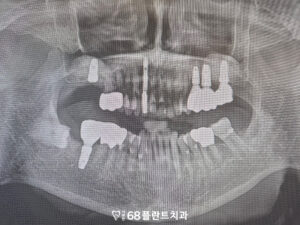

이후 임플란트를 순차적으로 식립하여

상실된 어금니의 기능을 하나씩

회복하는 과정을 진행했습니다.

상악동거상술로 충분한

뼈 높이가 확보된 뒤에는,

무리하지 않고 뼈가 견디는 범위 안에서

단계적으로 임플란트를

식립하는 것이 중요합니다.

이렇게 하면 초기 고정력

확보가 더 안정적이며,

치유 과정에서도 부담이 적어

장기적인 성공률을 높일 수 있습니다.

임플란트가 자리 잡기 시작하면서

상실된 부위들이 자연스럽게 채워지고,

전체적인 교합 균형도 점차 회복되어

환자분이 편안하게 씹을 수 있는

환경을 만들어 갈 수 있었습니다.

그리고 아래 어금니들도

크라운 치료를 시작하였습니다.